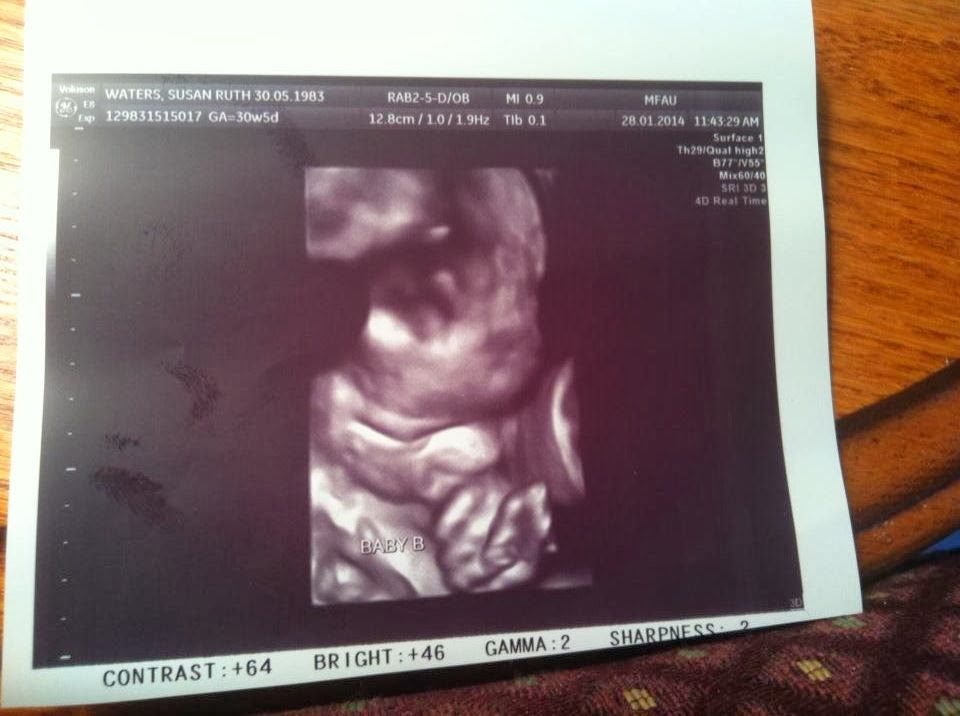

Look he’s sucking his thumb! Isn’t technology amazing to be able to capture this kind of stunning clarity? Susan had another ultrasound and here’s the baby boy…the baby girl is apparently not ready to have her photo so publicly displayed but they are both well.